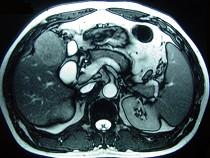

问题 男性,60岁,右上腹胀不适,右肝区叩击痛,影像检查如图,最可能的诊断是 ( )

选项 A、肝硬化、膈下脓肿 B、肝硬化、结节性增生 C、肝硬化、再生性肝癌 D、肝硬化、腹腔间质瘤 E、肝硬化

答案 C